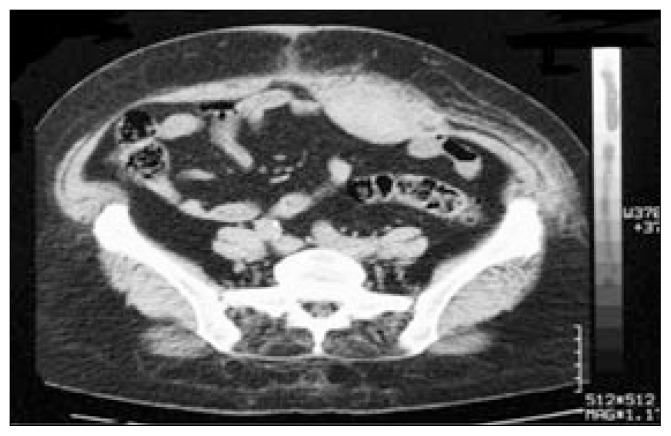

Abdominal ultrasonography (USG) was normal except for a suspect round hypoechoic image from the left upper to lower quadrants, and thus a thoracoabdominal computed tomography (CT) was obtained. Thoracoabdominal CT revealed an area of pneumonic consolidation on the left lung lower lobe and atelectasis, minimal pleural effusion and a hematoma of 8×27cm on the anterior wall of the abdomen and on the left side in the rectus abdominis muscle extending to the pubis (Figure 1). There was no acute pathology of the abdomen.

Figure 1.

CT scan of rectus sheath hematoma (patient 1).